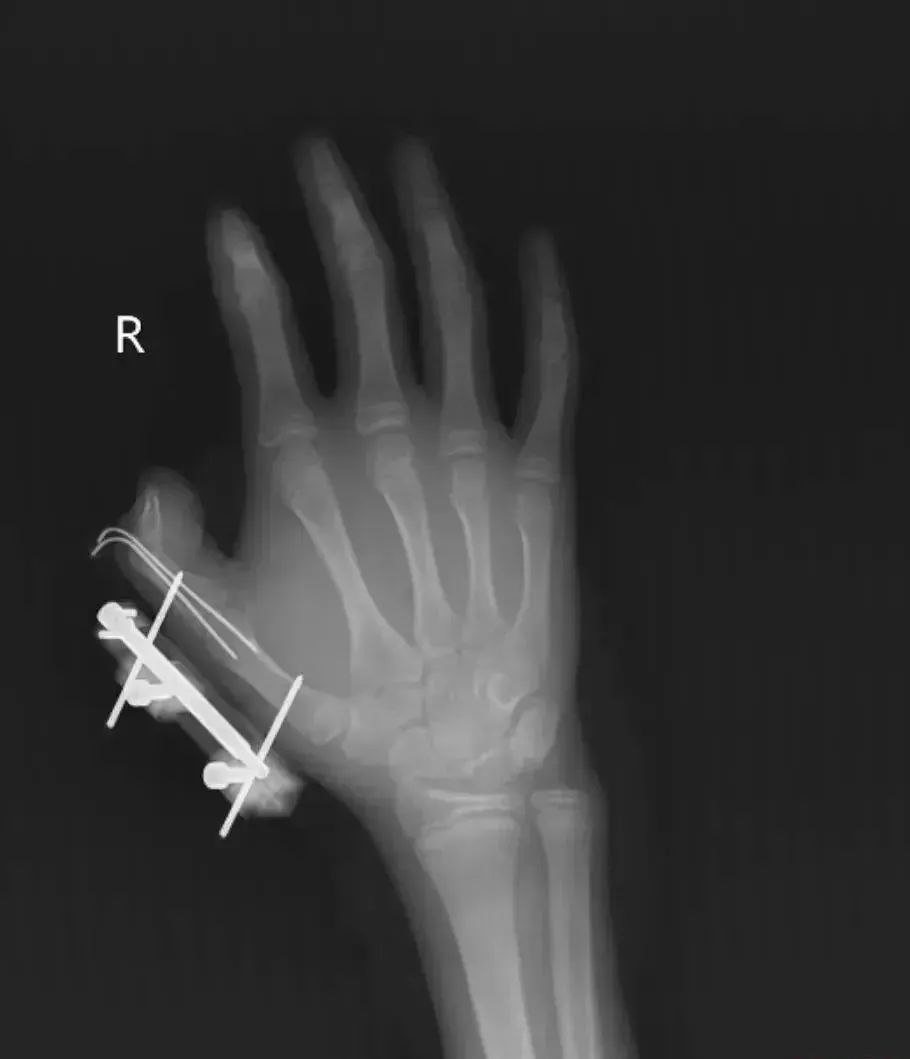

突然,密封袋里的干冰发生爆炸,维维的右手瞬间鲜血直流,拇指虎口处被撕开一道约10厘米的伤口,深可见骨,肌肉组织断裂外露,还伴随着拇指骨折、关节脱位,整个拇指完全失去知觉。

见状,家人赶紧带他到当地医院包扎,随后紧急转往湖南省人民医院手足显微外科。经治疗,维维的拇指保住了,但后续还需长期康复训练,才能慢慢恢复手部精细动作功能。